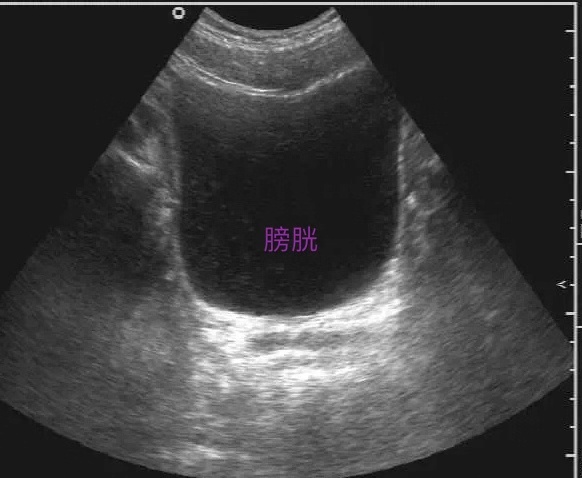

1. 膀胱

检查膀胱需要憋尿憋的刚刚好,才能更好观察膀胱壁的轮廓、连续性和完整性,厚度,内壁有无凹陷和隆起,有无占位性病变及其浸润程度。但不能过度,过度了也会产生假像。一般情况以喝完1000ml温开水后半小时检查为宜。